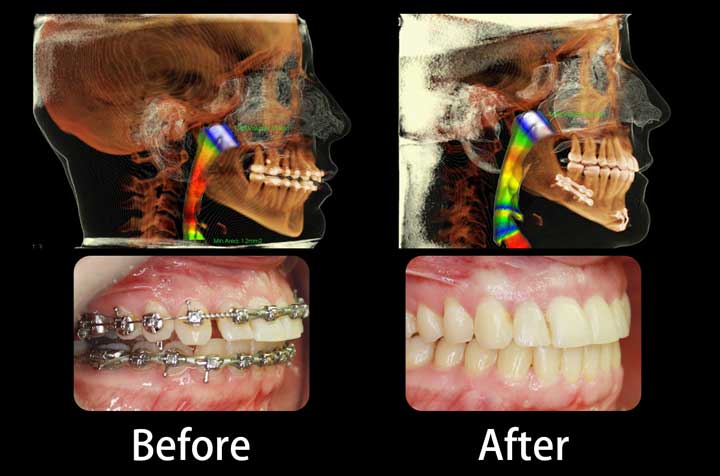

Corrective Jaw Surgery

Computer-planned orthognathic surgery to correct jaw misalignment, restore bite function, and achieve facial harmony. Dr. Antipov treats underbites (Class III malocclusion), overbites (Class II malocclusion), open bites, crossbites, facial asymmetry, and obstructive sleep apnea. Procedures include Le Fort I osteotomy (single-piece and 3-piece), bilateral sagittal split osteotomy (BSSO), genioplasty (chin repositioning), maxillomandibular advancement, and double jaw surgery. Every case uses 3D virtual surgical planning for millimeter-precise results.